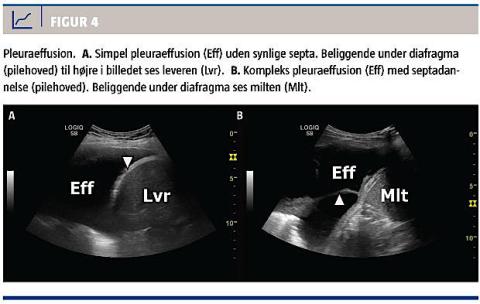

Parapneumonisk effusion og empyem

LUS giver en meget høj diagnostisk præcision ved diagnostik af pleuraeffusion, der er en hyppig komplikation i forbindelse med pneumoni [17]. Ved forekomst af pleuraeffusion med septa hos en patient med pneumoni, bør man have kompliceret parapneumonisk effusion og empyem in mente (Figur 4) [18, 19].

LUS kan dog ikke afløse diagnostisk pleuracentese med henblik på at differentiere imellem simpel parapneumonisk effusion, kompleks parapneumonisk effusion og empyem. Pleuracentese bør foregå ultralydvejledt, da der foreligger evidens for, at dette reducerer antallet af komplikationer [20].